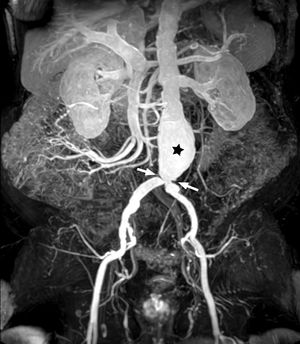

La dosis, volumen y velocidad de administración del CGd varían según se requieran estudios de perfusión de primer paso, de realce tardío o estudios de angiografía por RM (fig. 5), pero existen indicaciones estandarizadas según acuerdos de expertos que se recogen en la tabla 423,42,43.

Hepato-bilio-pancreáticoEl CGd extracelular es parte fundamental de la RM multiparamétrica (RMmp) hepato-bilio-pancreática, mediante un estudio dinámico T1-TEG con supresión grasa y obtención de imágenes basales precontraste, de administración del contraste (tabla 4) y adquisición poscontraste de, al menos, tres fases: arterial, venosa portal e intersticial o de equilibrio44 (fig. 6).